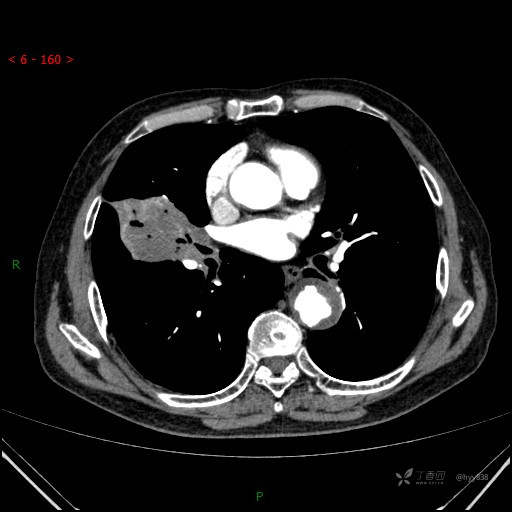

增强动脉期

静脉期